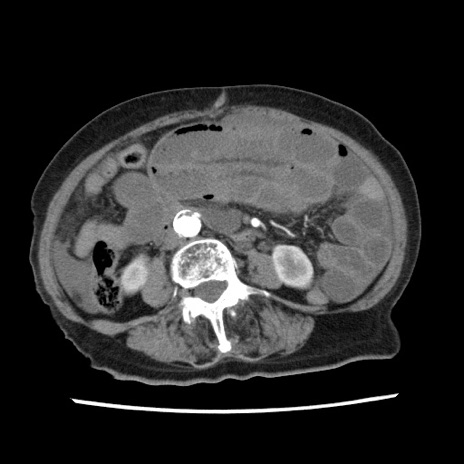

症例1(横断像)

【症例】80歳代女性

【主訴】腹痛

【現病歴】8時間前から腹痛あり来院。

【既往歴】糖尿病、脂質異常症、子宮体癌にて子宮全摘術

【身体所見】意識清明・会話良好だが腹痛で苦悶様、全腹部にわたって反跳痛と圧痛あり

【データ】WBC 13600、CRP 0.14、LDH 224、CK 90